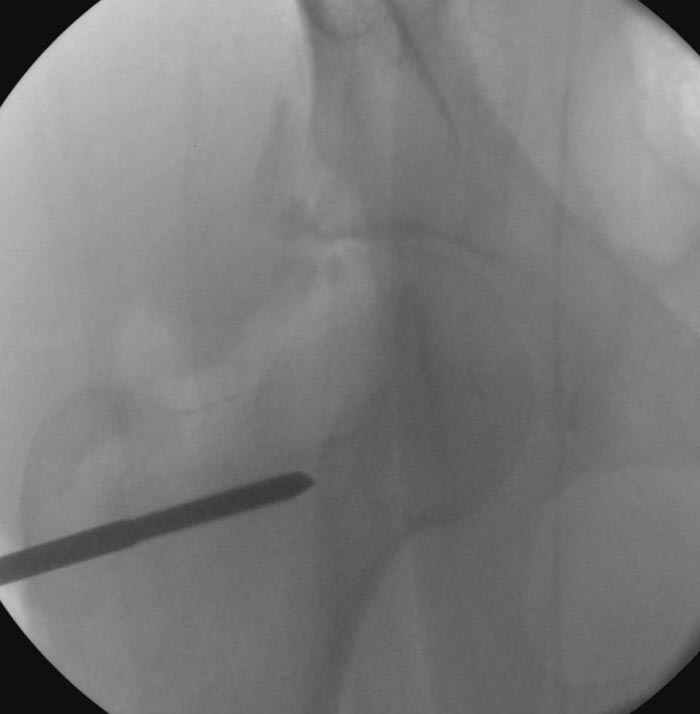

6:20 ответстенный врач принимает решение о репозиции в условиях операционной, предупреждаются родственники и больной, что при неудачной закрытой репозиции, о возможности открытой репозиции и фиксации задней стенки вертлужной впадины.

7:30 начало операции, больной на спине, попытка репозиции после анестезии N3, укладка больного на боку, доступ Kocher- Langenbeck, состояние седалищнего нерва около 2.5см кровоподтек, через joistick головка бедра приподнята, освобовождение сустава, фрагмент заднего края более 3х4 см репонирован на свое место. После промывания

Интраоперционные N5 косая запирательная и N6 подвздошный снимок